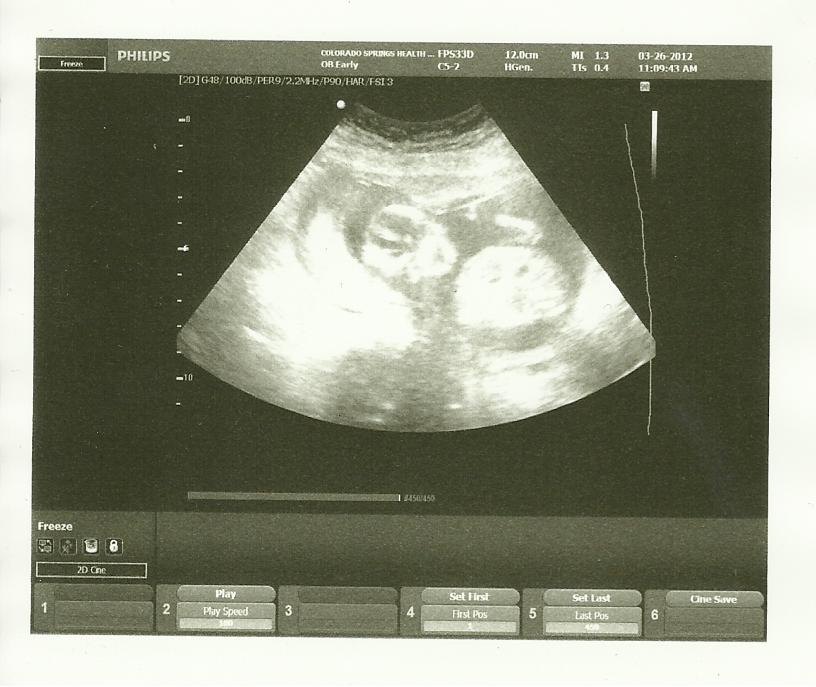

14w5d

Attachment 2239